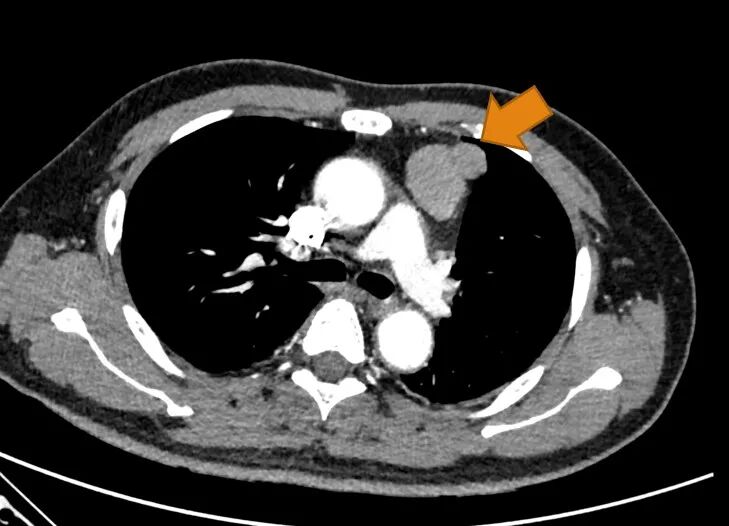

神经内科医生留了个心眼,还让老李做了个胸部CT。老李心生疑惑,说我好好的做什么胸部CT,不过还是听医生的话做了检查。

好家伙,胸腔里有一个直径3.6公分的肿块。

箭头所指为胸腺瘤

“你去胸外科吧。”神经内科医生对老李说道。